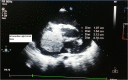

Primary cardiac tumour is a rare entity as secondaries in the heart are more common. A 2-year-old child was having repeated respiratory tract infection with poor oral intake and poor activity for 3 months. His symptoms progressed from New York Heart Association (NYHA) Class II to IV. On evaluation he had an intracardiac mass with extracardiac extension. Emergency tumour excision under deep hypothermic circulatory arrest was performed with provisional diagnosis of sarcoma. But Serum markers, histopathological examination and immunohistochemistry confirmed diagnosis of yolk sac tumour. Postoperative recovery was uneventful and the child was receiving adjuvant chemotherapy. Extensive literature review revealed only four cases of primary intracardiac yolk sac tumour published till date. Our case report is unique, in that intracardiac tumour had extracardiac extension by infiltration through right atrial wall. Previous four reports mention purely intracardiac mass.